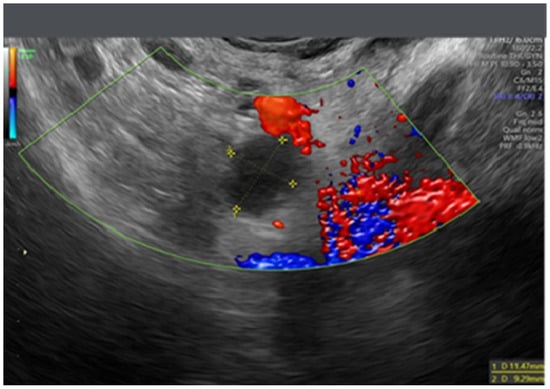

- Testa, A.C.; Ludovisi, M.; Savelli, L.; Fruscella, E.; Ghi, T.; Fagotti, A.; Scambia, G.; Ferrandina, G. Ultrasound and color power Doppler in the detection of metastatic omentum: A prospective study. Ultrasound Obstet. Gynecol. 2005, 27, 65–70. [Google Scholar] [CrossRef]

- Savelli, L.; De Iaco, P.; Ceccaroni, M.; Ghi, T.; Ceccarini, M.; Seracchioli, R.; Cacciatore, B. Transvaginal sonographic features of peritoneal carcinomatosis. Ultrasound Obstet. Gynecol. 2005, 26, 552–557. [Google Scholar] [CrossRef]

- Weinberger, V.; Fischerova, D.; Semeradova, I.; Slama, J.; Dundr, P.; Dusek, L.; Cibula, D.; Zikan, M. Prospective Evaluation of Ultrasound Accuracy in the Detection of Pelvic Carcinomatosis in Patients with Ovarian Cancer. Ultrasound Med. Biol. 2016, 42, 2196–2202. [Google Scholar] [CrossRef]

- Zikan, M.; Fischerova, D.; Semeradova, I.; Slama, J.; Dundr, P.; Weinberger, V.; Dusek, L.; Cibula, D. Accuracy of ultrasound in prediction of rectosigmoid infiltration in epithelial ovarian cancer. Ultrasound Obstet. Gynecol. 2017, 50, 533–538. [Google Scholar] [CrossRef]

- Fischerova, D. Ultrasound scanning of the pelvis and abdomen for staging of gynecological tumors: A review. Ultrasound Obstet. Gynecol. 2011, 38, 246–266. [Google Scholar] [CrossRef]

- Testa, A.C.; Ludovisi, M.; Mascilini, F.; Di Legge, A.; Malaggese, M.; Fagotti, A.; Fanfani, F.; Salerno, M.G.; Ercoli, A.; Scambia, G.; et al. Ultrasound evaluation of intra-abdominal sites of disease to predict likelihood of suboptimal cytoreduction in advanced ovarian cancer: A prospective study. Ultrasound Obstet. Gynecol. 2012, 39, 99–105. [Google Scholar] [CrossRef]

- Fischerova, D.; Zikan, M.; Semeradova, I.; Slama, J.; Kocian, R.; Dundr, P.; Nemejcova, K.; Burgetova, A.; Dusek, L.; Cibula, D. Ultrasound in preoperative assessment of pelvic and abdominal spread in patients with ovarian cancer: A prospective study. Ultrasound Obstet. Gynecol. 2017, 49, 263–274. [Google Scholar] [CrossRef]